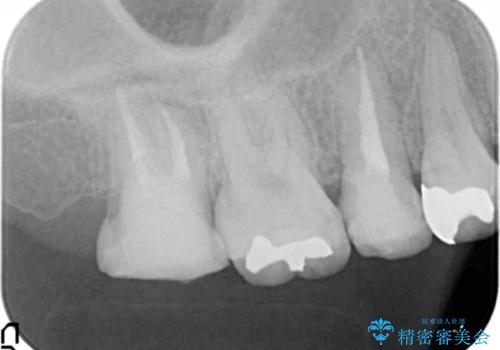

放置した虫歯を外科を行い抜歯を回避

- 放置していた虫歯が欠け、いよいよ怖くなり治療を希望され来院されました。

虫歯は、その進行度によりさまざまな治療法が提案されますが、

エナメル質・象牙質に限局する虫歯 →インレー修復

歯の神経に達する虫歯 →根管治療 クラウン補綴

歯ぐきよりも深い虫歯 →歯周外科による歯周環境の整備

を適宜行うことで良好な結果を得ることができます。

症状に応じて適切な処置を行ったことで、抜歯を回避し良好な結果を得ることができました。